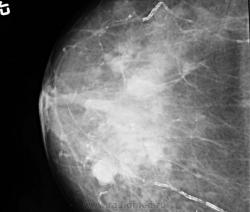

Бабуля 1926 г.р. сделала ММГ 1-й раз, жалобы на боли.

Похоже на локальную фиброзно-кистозную мастопатию, желательно бы еще выяснить нет ли у нее выделений из сосков и не было ли травмы мол. железы.

По всем канонам, и с учетом действующего приказа МЗиСР, пациентке обязаны делать биопсию, возможно под контролем УЗИ.